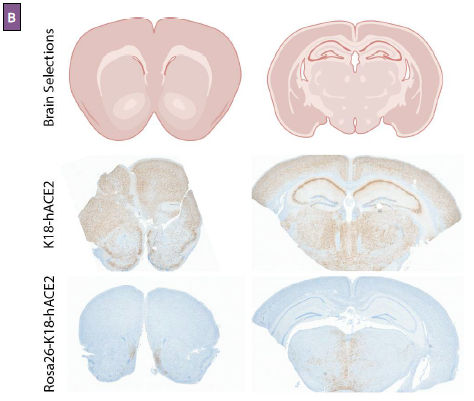

Figure 3: Fatal outcomes in Rosa26-K18-hACE2 mice are uncoupled from viral neuroinvasion. (A) Viral titers, determined by plaque-forming assay, in brain tissue at 2, 4, and 7-days post-infection. (B) Immunohistochemistry for SARS-CoV-2 Spike protein (brown stain) performed on coronal brain sections at 7 days post-infection. Reference brain sections are shown (top).